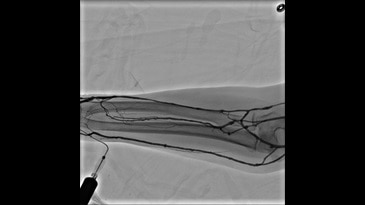

- Innova Breeze — простой и автоматизированный способ болюсного исследования. Модуль Innova Breeze для получения субтракционного периферического изображения с целью отслеживания контрастного вещества в реальном времени с возможностью изменения скорости перемещения стола. Возможен захват обеих конечностей одновременно с высоким разрешением сосудов малого диаметра. Независимый сдвиг пикселей позволяет сдвигать маску изображения обеих ног по отдельности, чтобы выровнять любые несовпадения.